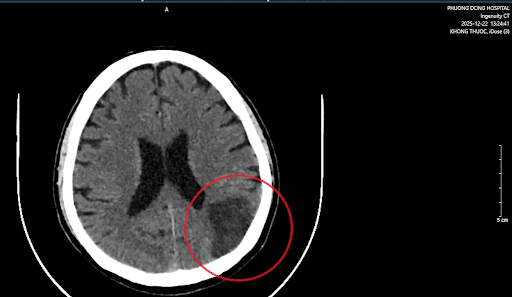

Vùng màu đen tương ứng vị trí nhồi máu của bệnh nhân trên phim chụp cắt lớp vi tính(CT) .